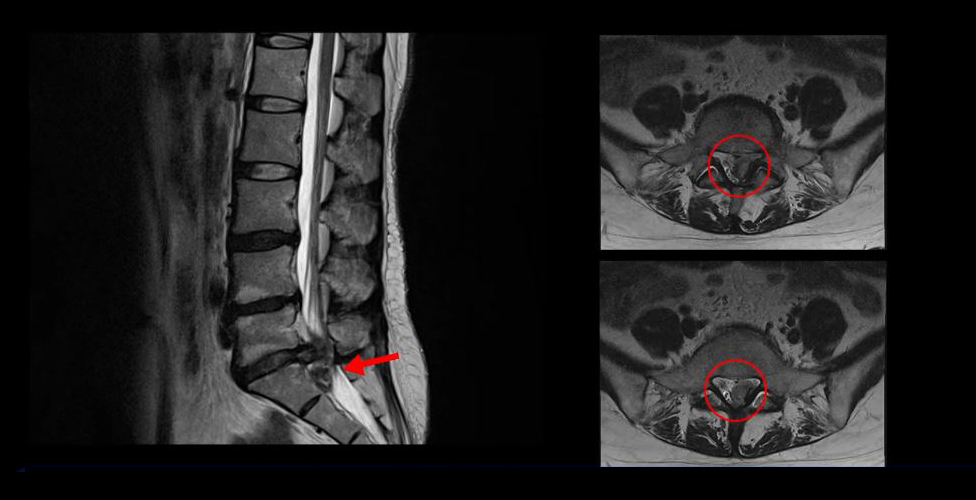

<5-1번 디스크 파열>

이 환자분의 허리 MRI를 보면 5번, 1번 디스크가 매우 심하게 터져 있는 것이 보입니다. 굉장히 심한 허리디스크터짐으로 인해 신경이 있어야 할 곳을 밀려나온 디스크 수핵이 거의 다 차지하고 있는 것을 볼 수 있습니다.

디스크가 심하게 터져서 수핵이 많이 밀려 나오니까 수핵이 위로도 밀려 올라가고 아래로도 흘러내려 있습니다.

축상면으로 보면 수핵이 위로도 밀려 올라가서 신경 공간을 까맣게 차지하고 있는 것이 보입니다.

아래로도 저 밑에까지 흘러내려가 신경 공간을 많이 차지하고 있어서 신경의 형태가 제대로 보이지가 않습니다.

MRI로 이 정도의 심한 파열이 보이면 다리에 마비나 대소변 장애까지도 있지 않을까 의심될 수 있는 상황인데요. 그래서 환자분이 MRI를 찍은 정형외과에서도 대소변 장애는 없는지 확인하였고, 파열이 심하니까 무조건 바로 수술을 해야 한다고 얘기했다고 합니다. 그런데 다행히도 이 환자분은 다리에 감각 마비와 보행 시 힘 빠짐 증상은 있으나, 대소변 장애는 없었습니다.